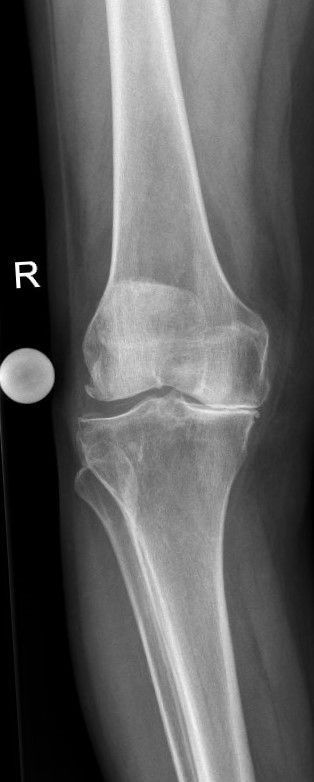

Prothetischer Gelenkersatz (minimalinvasiv) von Hüfte und Knie